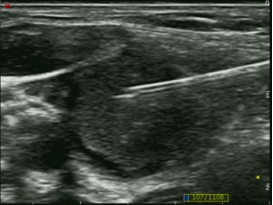

超声引导下经皮经肝胆囊穿刺置管引流术 超声引导下颈部肿物穿刺活检术 超声引导下肝肿瘤微波消融术